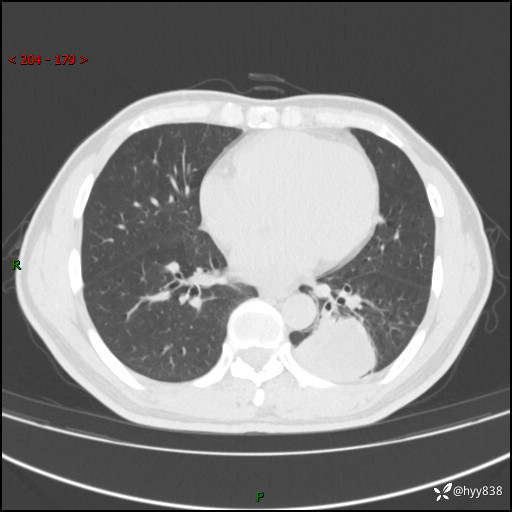

57岁/男,间断痰中带血1月余。纤支镜没有取到东西,穿刺轻松搞定---结果公布~

现病史:患者1月余前无明显诱因出现咯血症状,为痰中带血,量不大,伴轻度咳嗽,2024-3-26于当地市中医医院行胸部CT示:左肺下叶占位性病变。现患者仍有咳嗽不适,无发热乏力,无腹泻、便秘,无咳嗽,无头晕、无双下肢水肿等伴随症状,未行特殊治疗,今日患者再次出现咯血症状。患者为求进一步诊治,遂入我院,门诊以“肺脓肿”收入我科。 患者病程中,精神食欲可,二便正常,体力体重较前变化不明显。

增强

下肺占位,穿刺明确病理